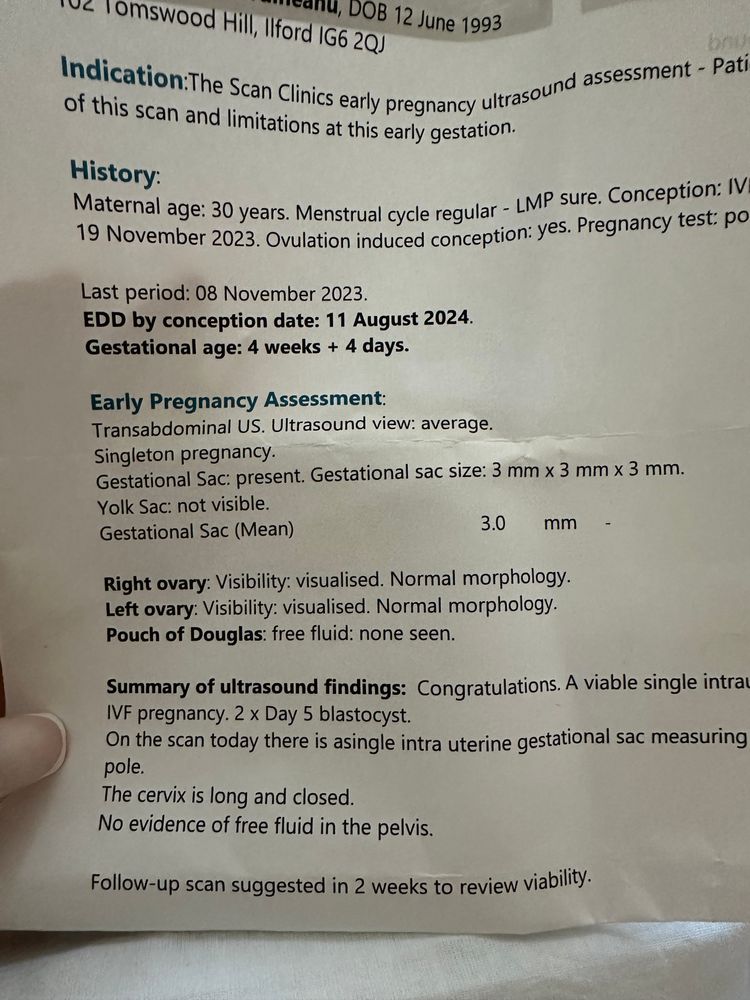

Здравствуйте девочки - вопрос возможно глупый но ситуация странная. Итак, в прошлую субботу мне исполнилось 3 недели после 5-дневного переноса эмбрионов. Итак, сканирование показало эмбрион размером 1,9 мм и плодное яйцо диаметром 9,5 мм. Я сдавала ХГЧ 4 раза за этот период и все в порядке. Вчера сделала сканирование (то есть через 4 недели после переноса) и уже виден только мешок 15,3 мм, а эмбрион исчез? Может ли быть такое - одну неделю эмбрион существует, а вторую неделю чудесным образом исчезает? У меня не было ни кровотечения, ни болей в животе. Прикрепляю фото первого скана с эмбрионом и второго вчерашнего скана без эмбриона. Врач рекомендовал мне продолжить лечение до следующего четверга и сделать еще одно сканирование через 5 недель после переноса. Любые предложения и советы будут оценены по достоинству. Большое спасибо

Ангелина, и сейчас прикреплю и рапорт где есть эмбрион

Ангелина, и сейчас прикреплю и рапорт где есть эмбрион